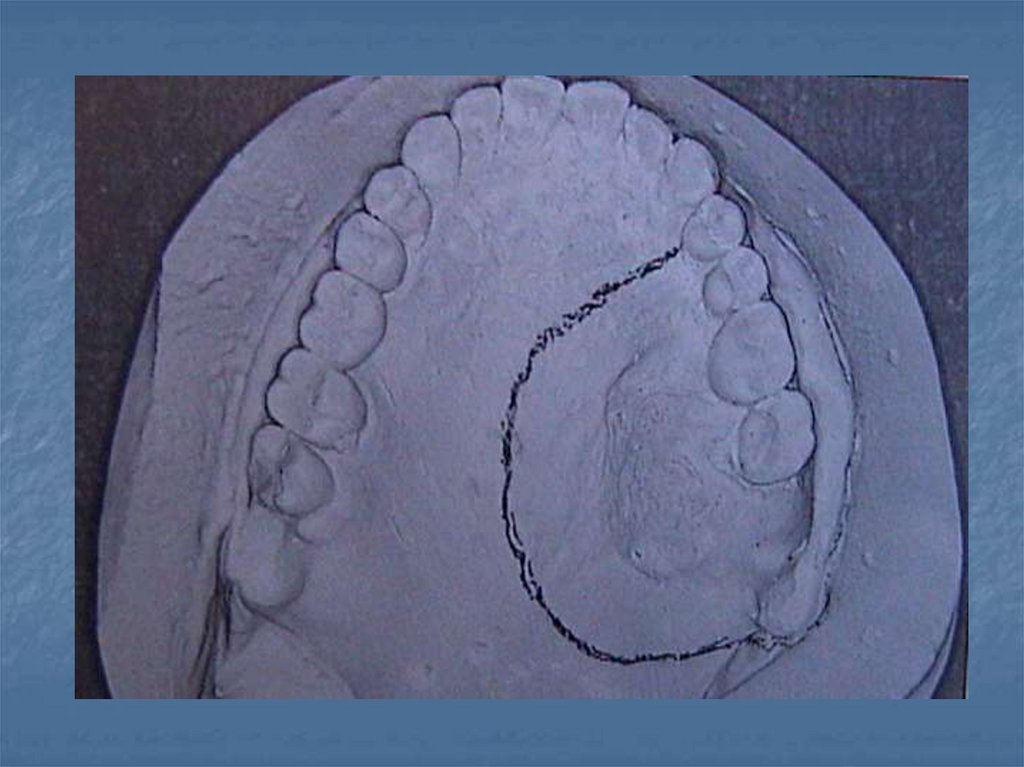

Obturatörleri Etkileyen Kuvvetler-2

ameliyat bölgesinin hijyenine olumlu katkılar sağlar

56. İmmediat protezlerin hazırlanması

Ölçü ameliyattan önce alınır.

Rezeksiyon bölgesi cerrah ile birlikte planlanarak model üzerine

işaretlenir

Rezeksiyon sahası içinde kalan Mevcut dişler tamamen kazınır. Dişsiz

alveol kavsi şekillendirilir.

Kretin vestibülü kazınarak derinleştirilir.

2mm kalınlığındaki pembe mum sağlam taraf dişlerinin palatinal

yüzeylerine kadar yayılarak modele edilir.

Tutuculuk için bükme kroşeler kullanılır. Protezin retansiyon ve

sustantasyonu sağlam taraftaki kroşelerle rezeksiyonun gerisinde

kalan maksiller tuber tarafından sağlanır

Kaide plağı şeffaf akriliten hazırlanır

Rezeksiyon bölgesinde kaldırılan dişler ya hiç konmaz ya da sadece

estetik amaçla ön dişler konabilir